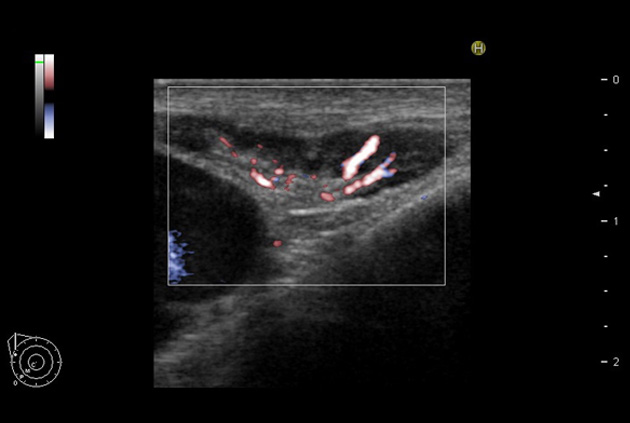

eFLOW

Provides clearer delineation between tissue and blood flow compared to conventional Color Doppler. Even low velocity flow can be imaged with high sensitivity.